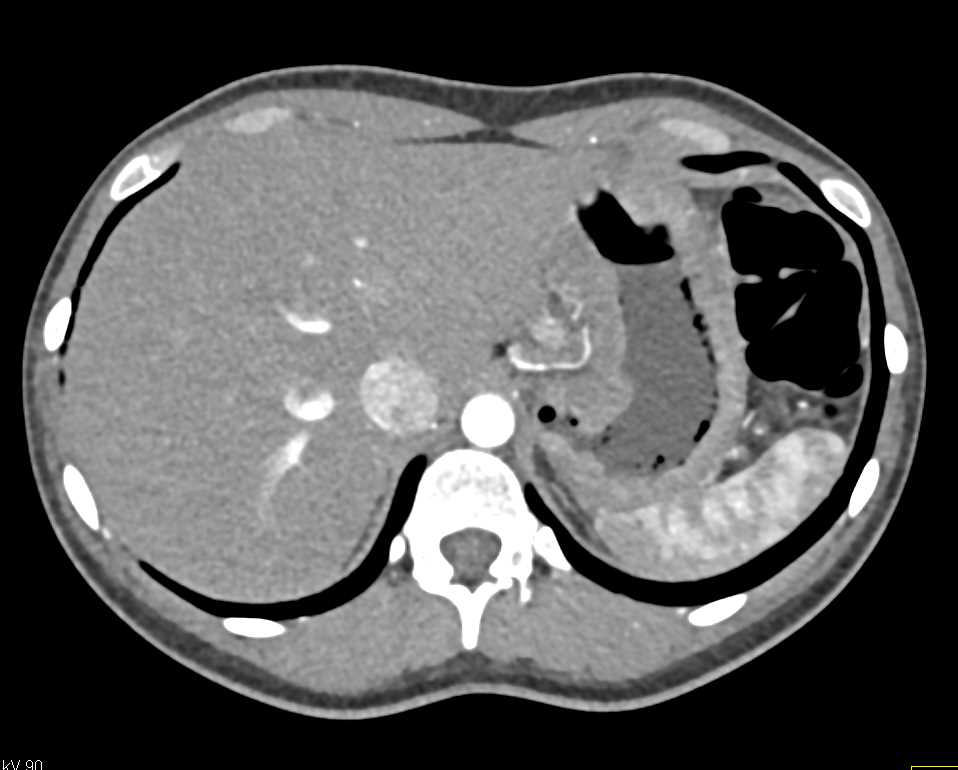

Infiltrating Carcinoma of the Gastric Antrum